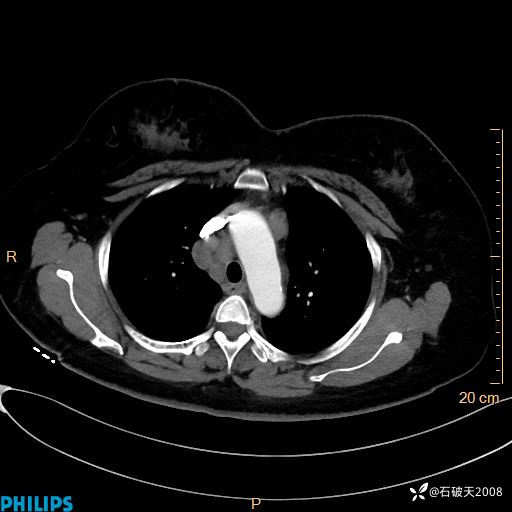

肺结节病?纵膈型肺癌?淋巴瘤?有点意思,欢迎围观

女 52岁 主 诉:咳嗽10余天,咳痰2天。

现病史:10余天前无明显诱因出现咳嗽,呈阵发性干咳,伴咽喉部发痒,无咽痛,无咳痰,无鼻塞、流涕、打喷嚏,无发热、畏寒、寒颤,无头痛、头晕,无胸闷、胸痛,无反酸、烧心,无腹痛、腹泻,无尿频、尿急,无皮疹等,在当地诊所求治,给予口服药物治疗(具体不详),病情无好转。遂在当地社区卫生服务中心开具口服药物治疗(具体不详),疗效欠佳。2天前出现咳痰,在我院门诊求治,行胸部CT提示肺部感染,建议住院,患者要求口服药物治疗,目前仍咳嗽、咳白色粘痰,白天量多,夜间自觉喉部喘鸣音,遂再次来院就诊,以“肺部感染”为诊断收入院。发病以来,神志清,精神可,饮食可,夜间睡眠差,大小便正常,近期体重无明显变化。

肺窗